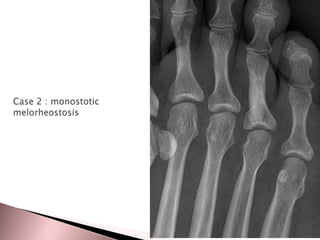

Case 3 : monostotic

melorheostosis

•May be monostotic or polyostotic

It has a predilection for long bones of the limbs ,it can be seen

almost anywhere

Hands and feet are not infrequently involved ,and involvement of the

axial skeleton is rare

Sclerotic lesions of cortical bones, usually in the diaphysis,

that resemble “candle-wax-dripping”

Cortical hyperostosis with an undulating appearance usually

affecting one side of a bone